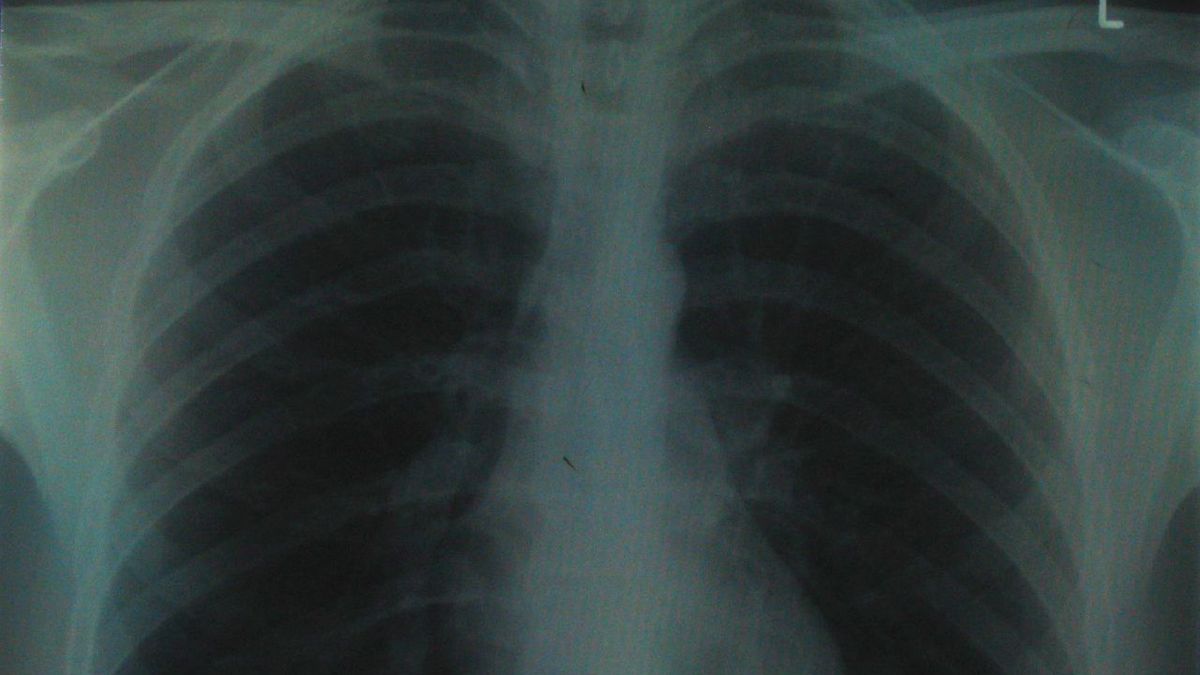

W przyszłości chore płuca wymienimy na nowe - sztuczne

W przyszłości chore płuca wymienimy na nowe - sztuczne 1fot. Flickr.com/Aidan Jones/lic. CC